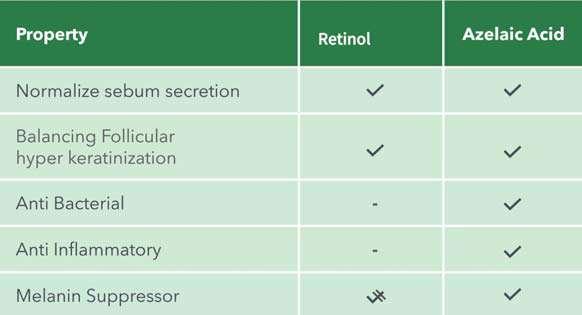

Azelaic acid is widely recognized for its ability to:

Regulate the rate and pattern of cell proliferation in the epidermis

Balance sebum production

Provide antibacterial effects

Act as an anti-inflammatory agent

Suppress melanin production. In addition, it is also considered an antioxidant and has been found to have a beneficial effect on mature skin as it induces the production of collagen and hyaluronic acid.

When doctors prescribe products for acne patients to use at home, these will usually be topical (or oral) retinoids, and/or topical or oral

antibiotics, or benzoyl peroxide. If we compare azelaic acid to topical retinoids, which are also available to us as skin practitioners (retinol and its derivatives), it seems that azelaic acid is more versatile and treats more acne pathologies.

Retinol and its derivatives balance sebum secretion and normalize skin cell turnover. Azelaic acid does this effectively, but in addition it is also anti-bacterial and anti-inflammatory. And if we consider the possibility of PIH after acne, azelaic acid suppresses melanin production and can minimize the appearance of this type of pigmentation.